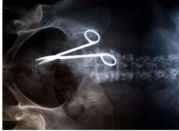

Я в спортзал хожу давно, и некоторых людей вижу там по много лет, и по несколько раз в неделю. И мы уже немножко познакомились, и изредка болтаем. И вот один - бизнесмен сорока пяти лет - три месяца назад пожаловался, что ему будут оперировать коленку. Раньше он играл в футбол, ...